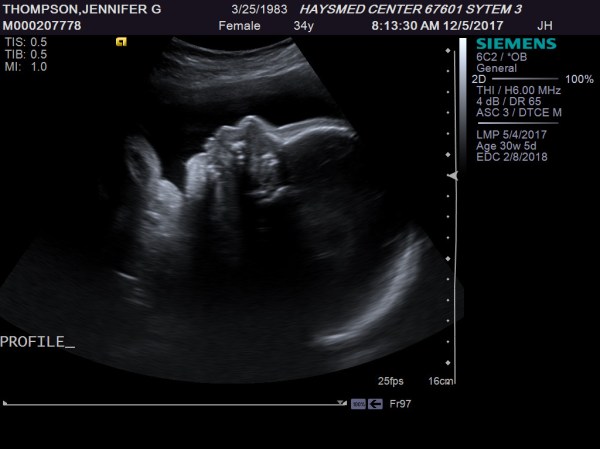

Why my body treats pregnancy like a bad blind date—bolting for the exit before the appetizers arrive—is one of life’s more baffling mysteries. My babies always emerge from the chaos strong, healthy, and perfect as polished trophies, yet my womb seems to regard the whole affair as an unwelcome intrusion, ejecting its precious cargo weeks ahead of schedule. It’s a wretched mismatch, like a marathoner cursed with shoes two sizes too small. That premature arrival turned our world into a 21-day gauntlet of beeping monitors, tiny incubators, and the kind of bone-deep terror that makes every sunrise feel like borrowed time. Touch-and-go doesn’t begin to cover it. He’s thriving now, of course—my little sprinter, outpacing the odds—but those NICU nights remain the slowest, most grueling miles I’ve ever logged.

As I sit here this morning watching coverage of Hurricanes Irma and Jose, images of 9/11, and my son playing in the foreground, the fact that I am extremely lucky does not escape me. We are safe, dry, warm and happy here in Hays, Kansas. I have food to feed my pets and family. We have cars to get us where we need to go, and this warm cup of coffee makes for a great start to my day. Granted, this baby in my belly sure is making my stomach growl right now, but I plan to get up and take care of that in a few minutes.

The year 2017 has been filled with a lot of heartache, as far as I am concerned. As summer approaches, I continue to hope for better things on the horizon, and I think they are out there. We have had some interesting developments since my last post, so I decided I would take a few minutes to share them with you.

From mile 8 to mile 18 (week 13-27), things start to go numb. Things hurt occasionally, but you are sort of in your groove, and the crowd of excited fans has finally thinned out a little bit. You realize that there is no turning back now, so you are basically just going through the motions attempting to make it to the next mile (or milestone). With every gel, your energy level increases for a bit, and you feel like you can actually accomplish something here.